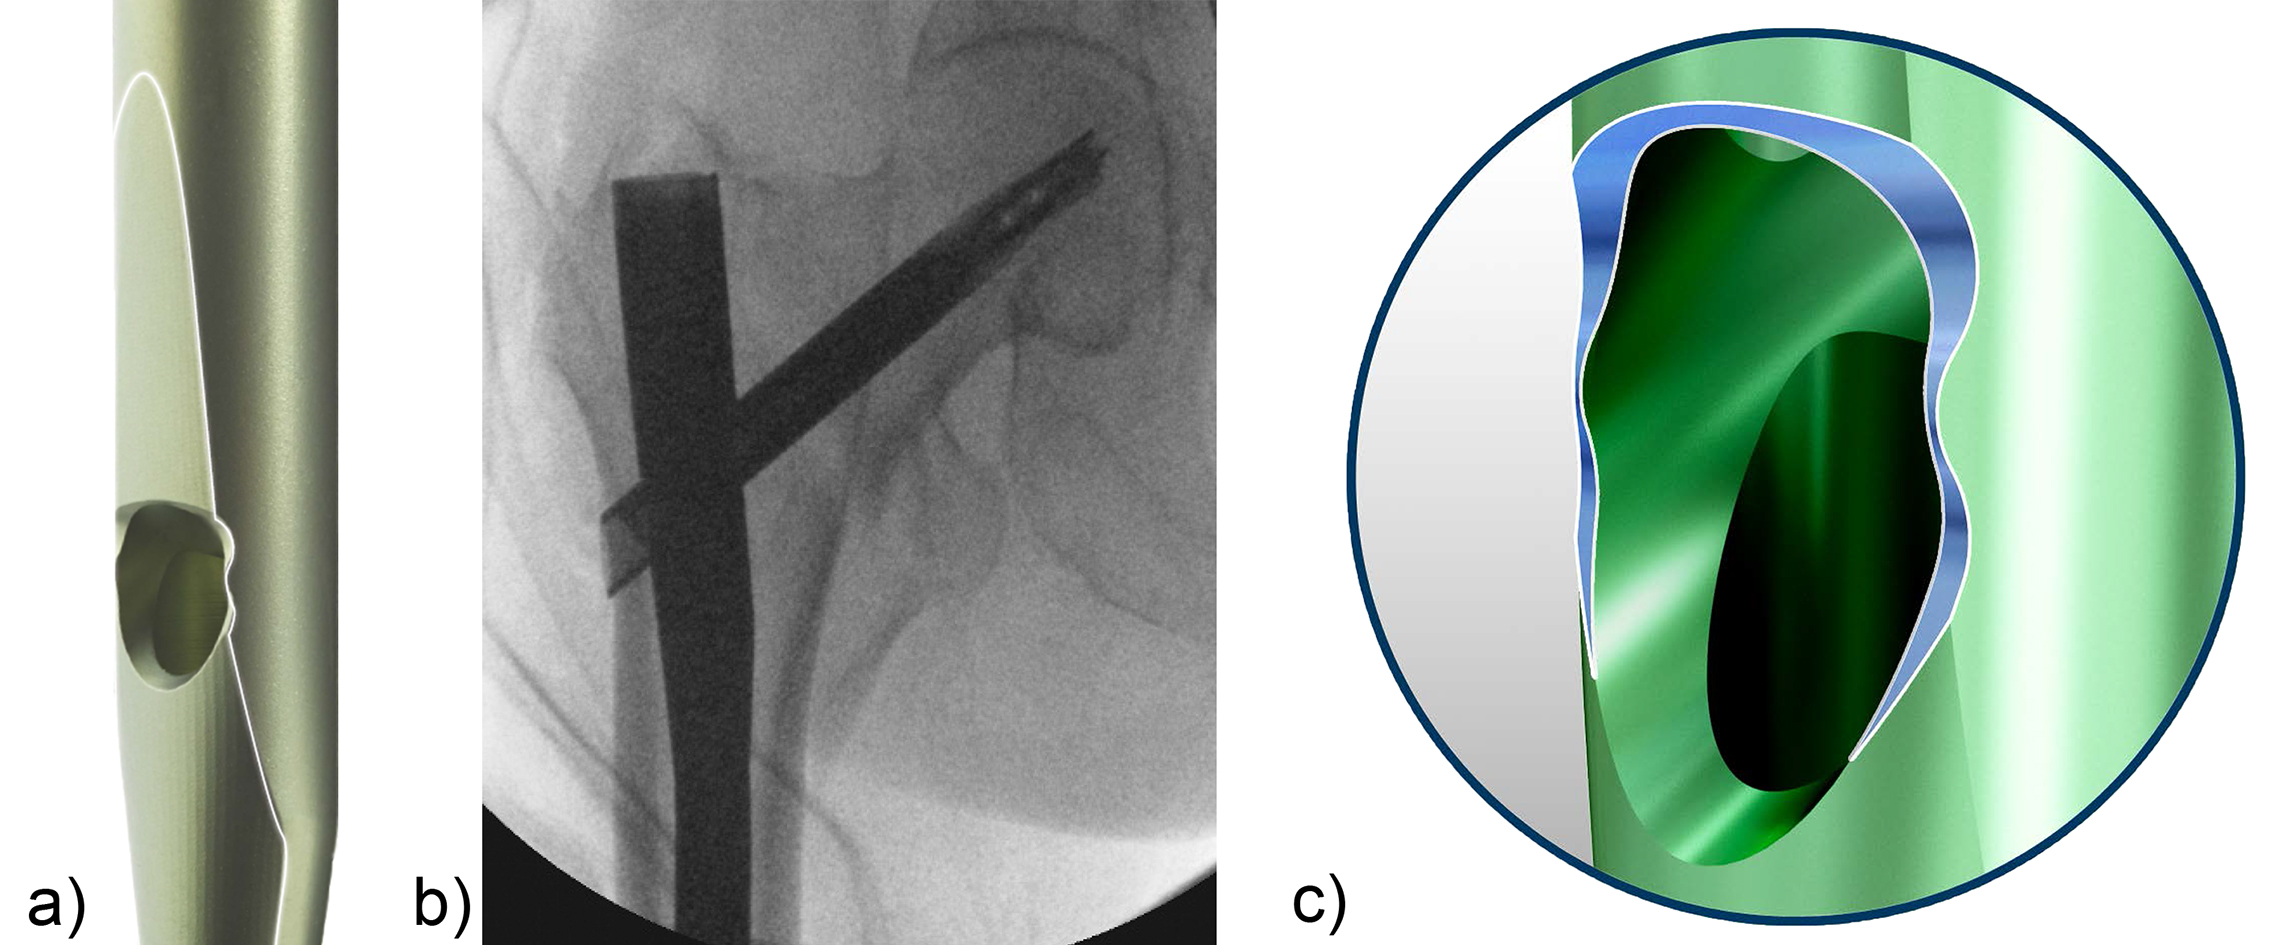

QUICK CLICK self-retaining technology

The QUICK CLICK self-retaining technology (Fig 1) is designed for easier and safer attachment of the nail to the insertion handle. An optional percutaneous set with larger instruments including protection sleeve and insertion handle are available for large stature patients. Another important feature of the instrumentation is its ability to enable interfragmentary compression when used in conjunction with a compression nut after rotation has been locked. Matching internal threads in implant and removal instruments facilitate implant removal.

The TFNA offers surgeons the option to insert either a blade or a screw head element. The TFNA helical blade is designed to compress bone during insertion, which enhances implant anchorage and can reduce the risk of cut-out. As such it is regarded as particularly advantageous under osteoporotic bone conditions. However, there are still many surgeons that prefer to use the TFNA screw as the head element regardless of bone quality. Since these surgeons do not necessarily need the instrumentation that allows the insertion of either the blade or the screw, a screw-only aiming arm has been developed to further reduce instrument complexity and cost.

The screw-only aiming arm is offered for CCD angles of 125° and 130° (Fig 2). It has a coaxial locking mechanism that reduces the size of the aiming arm and decreases its foot-print in the instrument case (Fig 3). It presents the possibility of inserting the screw-only sleeve and locking it with just one hand. Interfragmentary compression is possible by means of a compression nut (Fig 4).